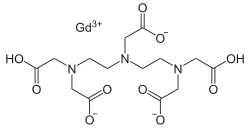

- Magnetresonanztomographie

Die Magnetresonanztomographie (MRT) ist als bildgebendes Verfahren zu unempfindlich, um die Passage von Wirkstoffen in das Gehirn darzustellen. Völlig anders ist die Situation bei einer geschädigten Blut-Hirn-Schranke. In diesen Fällen spielt die kontrastmittelunterstützte MRT als diagnostisches Verfahren bei verschiedenen neurodegenerativen Erkrankungen und Krebserkrankungen im Bereich des Gehirns eine wichtige Rolle. Dies wird im Kapitel der mittelbar mit der Blut-Hirn-Schranke assoziierten Erkrankungen ausführlicher beschrieben.

Bereits kurz nach der Entwicklung von Gadopentetat-Dimeglumin (Gd-DTPA), dem ersten Kontrastmittel für die Kernspintomographie, 1984,[236] wurde das Potenzial der kontrastmittelverstärkten Magnetresonanztomographie für die Diagnose von lokalen Störungen der Blut-Hirn-Schranke erkannt.[237] Gd-DTPA ist als hochpolares Molekül viel zu hydrophil, um die gesunde Blut-Hirn-Schranke passieren zu können. Veränderungen an den Tight Junctions, wie sie beispielsweise durch Glioblastome ausgelöst werden, ermöglichen den parazellulären Transport dieses Kontrastmittels in das Interstitium. Dort verstärkt es durch die Wechselwirkung mit den Protonen des umgebenden Wassers den Kontrast und macht so die defekten Bereiche der Blut-Hirn-Schranke sichtbar. Da diese Blutgefäße für die Versorgung des Tumors zuständig sind und sich zu diesem in unmittelbarer Nachbarschaft befinden, lässt sich so das Ausmaß des Tumors darstellen.